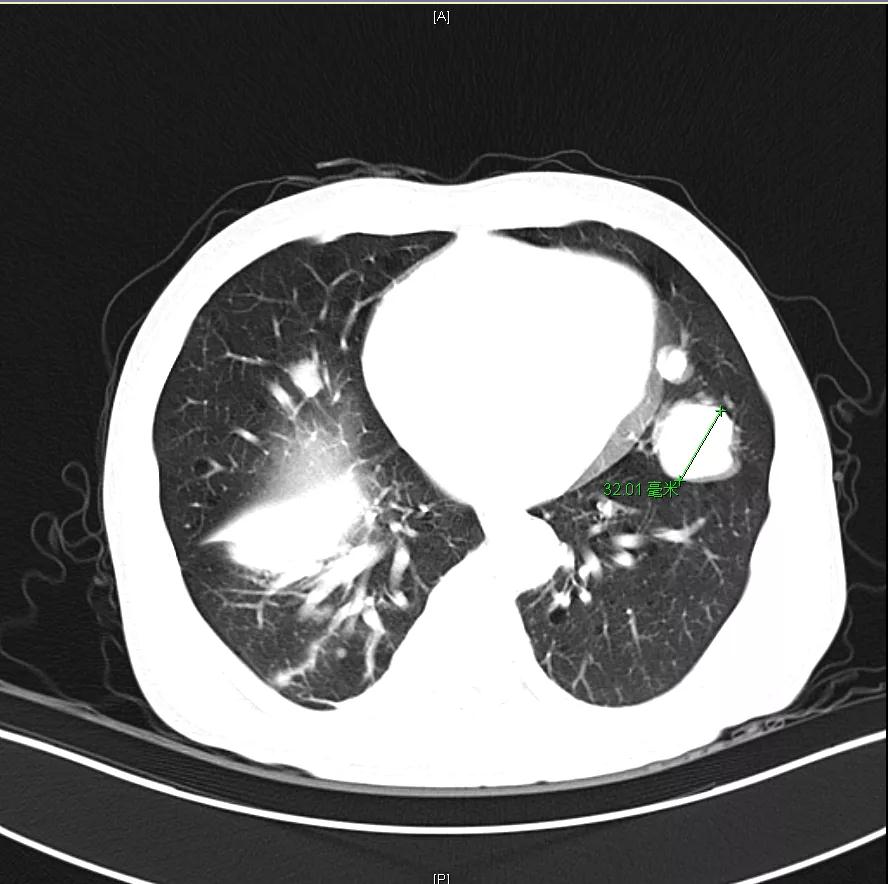

肝脏弹性超声:12kPa。腹部MRI平扫+增强:肝巨块结节性HCC(最大径18.4cm)伴肝内多发转移(最大径3.5cm),肝右静脉广泛癌栓形成;肝硬化伴门脉高压、脾大、少量腹水;肝囊肿;双肺多发转移。胸部CT平扫:两肺多发转移,两肺气肿伴肺大泡,两肺散在慢性炎症,右侧少量胸水。

Δ肺CT:双肺多发转移